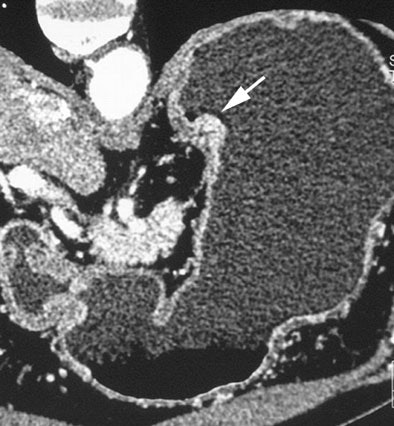

| Early gastric cancers. A 69-year-old man with protruding type of early gastric cancer. Oblique multiplanar reconstruction perpendicular to gastric wall shows protruding mass (arrow) of gastric cardia. Fig. 2A, Shimizu K, Ito K, Matsunaga N, Shimizu A, Kawakami Y. "Diagnosis of Gastric Cancer with MDCT Using the Water-Filling Method and Multiplanar Reconstruction: CT-Histologic Correlation" (AJR 2005; 185:1152-1158). |

The results were well-correlated with pathologic findings, and the overall accuracy of CT staging was 85%, they noted. On histology a high-attenuating abnormal inner layer corresponded to close proliferation of cancer cells, mainly mucosal and submucosal, whereas low-attenuating areas were indicative of scattered cancer cell diffusion such as in the proper muscle with dermoplastic changes and inflammatory reaction.

"In our seven early gastric cancers detected at MPR but not visible on 5-mm-slice axial images, six were located at the large or lesser curvature of the gastric angle or antrum," the group wrote. "Detection of early gastric cancers with 5-mm-slice axial images may be difficult because of partial volume artifacts where the gastric wall is tangent to the axial scan, such as the greater or lesser curvature of the gastric antrum or angle."

The overall detection rate for gastric cancers was 65%, including 96.2% (25/26) advanced cancers (pT2-pT4) and 41.2% (14/34) early cancers, the team reported. There was a statistically significant difference (p < 0.05) in the detection rate of early cancers between thin-slice MPR images and 5-mm axial slice images, but not between 5-mm axial images and 5-mm MPR images.

"In 34 early gastric cancers, thin-sliced MPR images depicted 68.8% of submucosal cancers ... and they showed 16.7% (3/18) of less invasive mucosal cancers," the researchers wrote. "The detection rate for grossly nonprotruding early cancers was comparatively low (28.6%)."